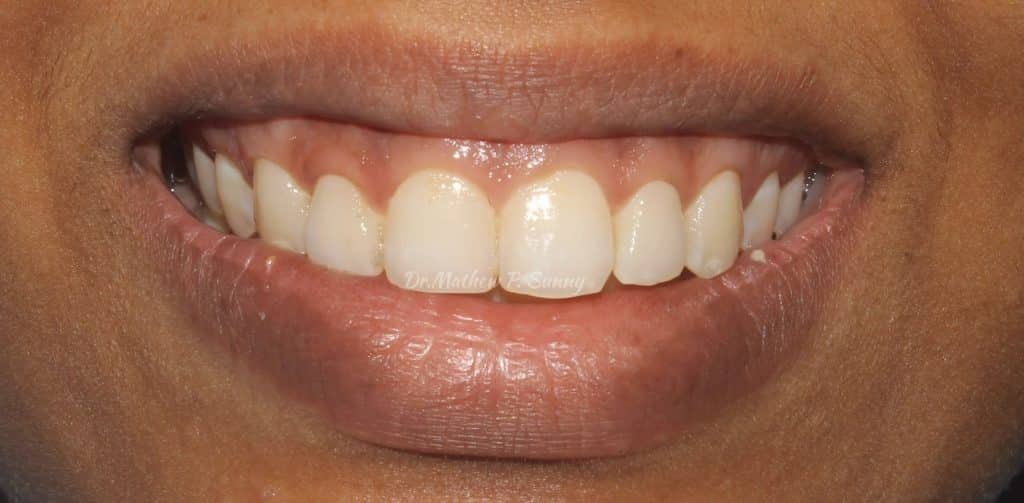

immediate post op smile..

healing at 1 month.. showing better tissue contour and good exposure of crowns..